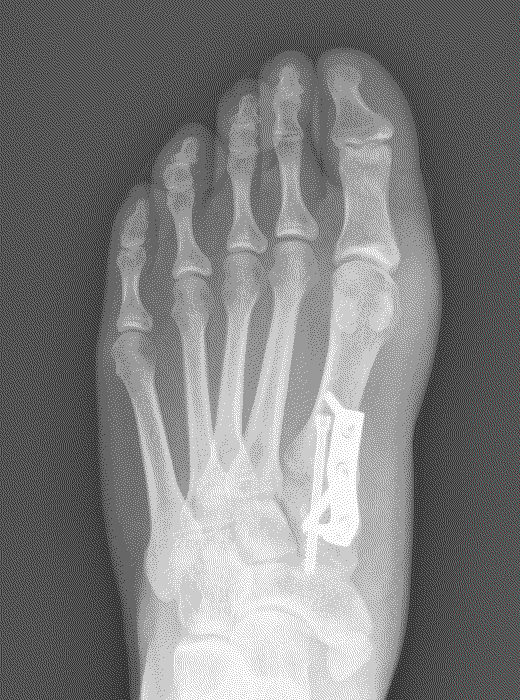

This is an osteotomy in the metatarsal head (transposition), the metatarsal head is moved to correct the deformity and fixated with a single screw. It is indicated for mild to moderate deformities. The choice to carry out a Scarf or a capital osteotomy will be made by your consultant.

This is a transposition osteotomy. It is normally indicated for mild to moderate deformities. The new position of the first metatarsal is maintained with two screws which enables stability.

This involves a fusion of the first metatarsal cuneiform joint, allowing the first metatarsal to be rotated back into a straight position. It is normally reserved for severe deformities. Once the corrected position has been obtained it is usually maintained with a plate and screws.

The ‘Akin’ Osteotomy is combined with a Scarf, capital or Lapidus to improve alignment of the big toe. A small wedge of bone is removed and fixed with a wire. This does not change the post-operative regime.